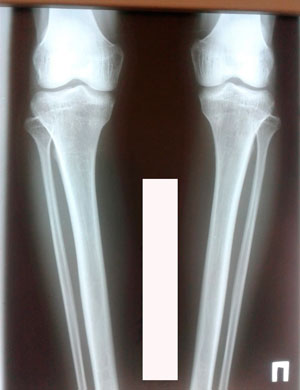

Исходник - 32 года.

Дата операции 28.01.2020

IMG_8501-28-01-20-12-28.JPG

IMG_8506-28-01-20-12-28.JPG